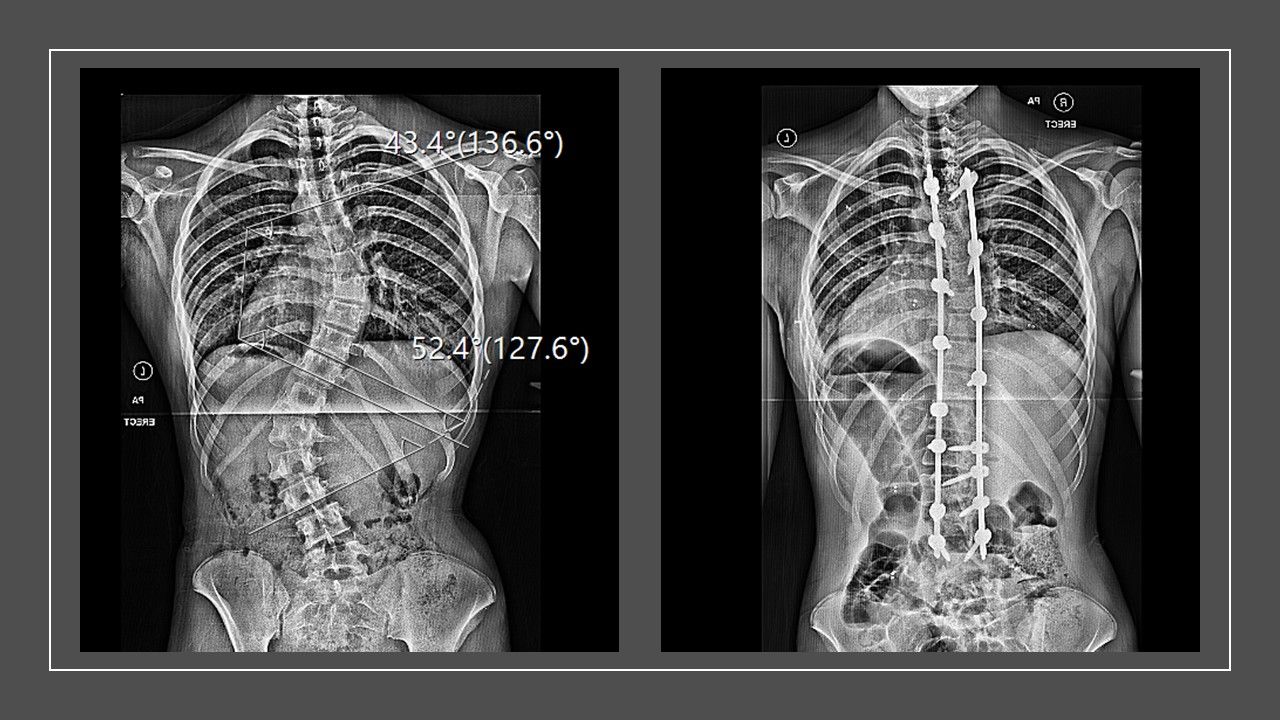

Unfortunately, the brace wasn’t enough to slow the progression of the curve, which threatened to compress her organs and reduce her lung capacity.

Just two weeks after completing her GCSEs, Phoebe underwent a six-hour spinal fusion surgery at Evelina London Children’s Hospital, part of Guy’s and St Thomas’ NHS Foundation Trust.

Surgeons fused her spine from the T4 to L4 vertebrae – essentially from just below her collarbones to her lower back – using titanium rods to stabilise her spine.

The surgery left her unable to bend her spine and only able to hinge at the hips – but it also made her two inches taller.